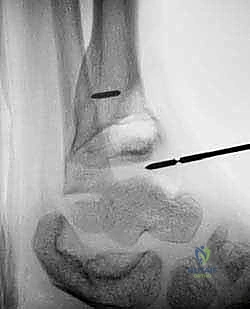

الخطوة الثانية: الاستئصال الدقيق (Burring)

باستخدام مثقاب جراحي دقيق جداً (High-speed burr) ومجارف جراحية صغيرة (Curettes)، يبدأ الدكتور هطيف بإزالة الجسر العظمي الصلب تدريجياً. يتم ذلك تحت توجيه الأشعة السينية المستمرة في غرفة العمليات (C-arm Fluoroscopy) لضمان إزالة العائق بالكامل وعدم المساس بالخلايا السليمة.